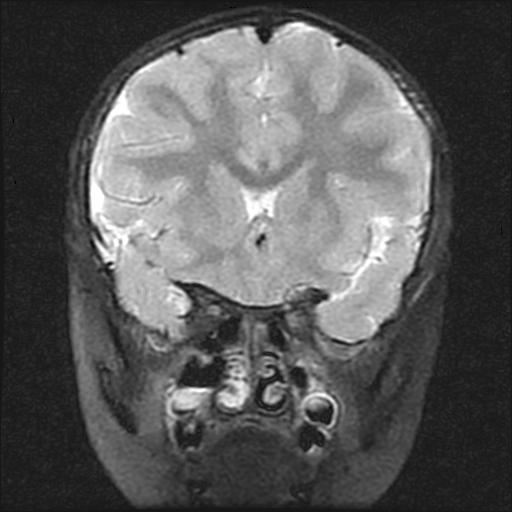

6岁小儿,左侧视神经瘤术后。现左侧视力减退。